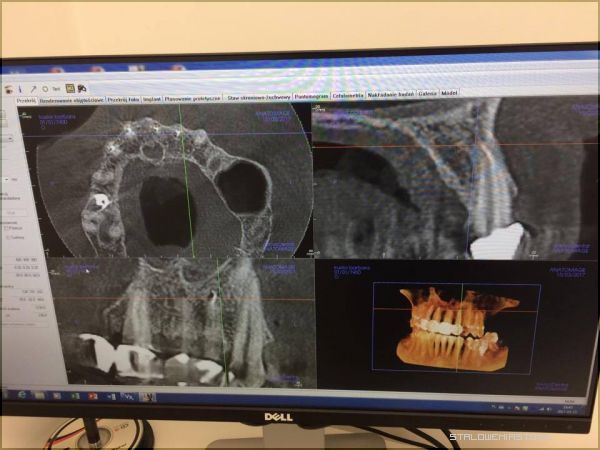

Świat zaczyna się w Stalowej WoliStomatolog Piotr Trafidło znany jest z tego, że w swojej pracy posługuje się urządzeniami i materiałami z najwyższej półki. Nie dziwi więc fakt, że w Centrum Precyzyjnej Stomatologii Multident pojawił się właśnie supernowoczesny sprzęt, na którym pracują stomatolodzy tylko w najlepszych klinikach Europy. Tego typu urządzenia w Polsce wciąż należą do rzadkości. Mowa tu o nowoczesnym tomografie umożliwiającym pozyskiwanie obrazów z rekonstrukcją 3D do aktualnie wykonywanych zabiegów. Aparat Gendex pozwala również na zmianę dawki promieniowania RTG, poprzez wykonywanie radiogramów dostosowanych do rozmiarów ciała. Jest więc bardzo bezpieczny dla pacjenta. Wykonuje zdjęcia najwyższej jakości. Dzięki niemu można precyzyjnie i szybko określić przyczynę dolegliwości, obejrzeć zęba w każdej płaszczyźnie, wykonać symulację komputerową i dotrzeć do źródła problemu bez eksperymentowania i przewidywania. Leczenie wówczas staje się tak precyzyjne, że nie ma tu możliwości popełnienia błędu przy stawianej diagnozie, a takie błędy mogą się zdarzyć, gdy korzysta się ze zwykłego aparatu RTG. Tomograf wyposażony jest również w cefalometrię co umożliwia bardzo dokładną diagnostykę wad ortodontycznych oraz zaplanowanie najlepszego leczenia ortodontycznego.

Bo diagnostyka jest najważniejszaW XXI wieku nie jest sztuką skorzystanie z pomocy stomatologa. Sztuką jest wybranie takiego gabinetu, gdzie nasze problemy zostaną rozwiązane kompleksowo, bezpiecznie, a przede wszystkim niezwykle dokładnie. Piotr Trafidło od wielu lat pracuje jako implantolog. W swojej karierze zawodowej ma na koncie blisko 2 tysiące udanych zabiegów implantologicznych. Jest „autorem” wielu uśmiechów na Podkarpaciu. Tomograf 3D pomoże mu w jeszcze lepszej diagnostyce, dzięki czemu możliwe będzie np. określenie grubości i gęstości kości, a co za tym idzie, dobranie najlepszego dla danego pacjenta implantu. Pojawienie się takiego urządzenia w Multident to rewolucja na rynku medycznym w regionie. Skuteczność leczenia będzie teraz tak duża, że firma może w ciemno zagwarantować, że w sytuacji gdyby implant jakimś cudem się nie przyjął, pacjent będzie mógł otrzymać stuprocentowy zwrot kosztów leczenia.

Urządzenie może stanowić nieocenioną pomoc również dla laryngologów w rozpoznaniu chorób zatok, nosa i gardła. Dla pacjenta najważniejszą informacją jest fakt, że w przypadku diagnostyki Tomografem 3D Gendex dawka promieniowania RTG jaką otrzymuje podczas badania jest ok. 10 razy mniejsza w porównaniu do tomografii klasycznej.